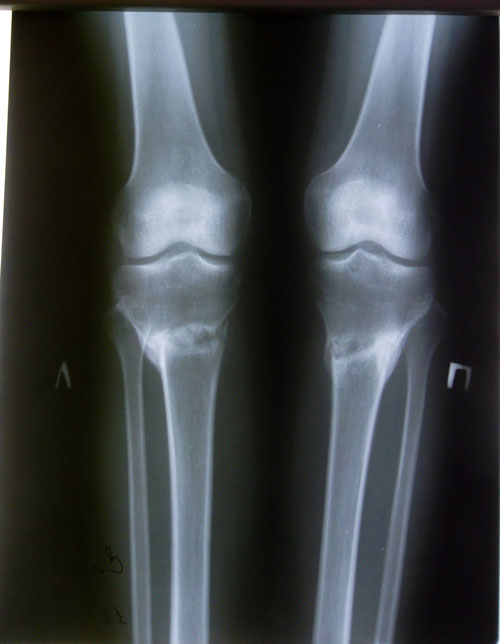

Рентген в 1,5 месяца после снятия аппаратов.

Здравствуйте, Симона! По результатам рентгеновских снимков, поберегитесь ещё месяц от физ. нагрузок и тяжестей. А так, всё хорошо! Через 1,5 месяца ждём повторный рентген. animashka179